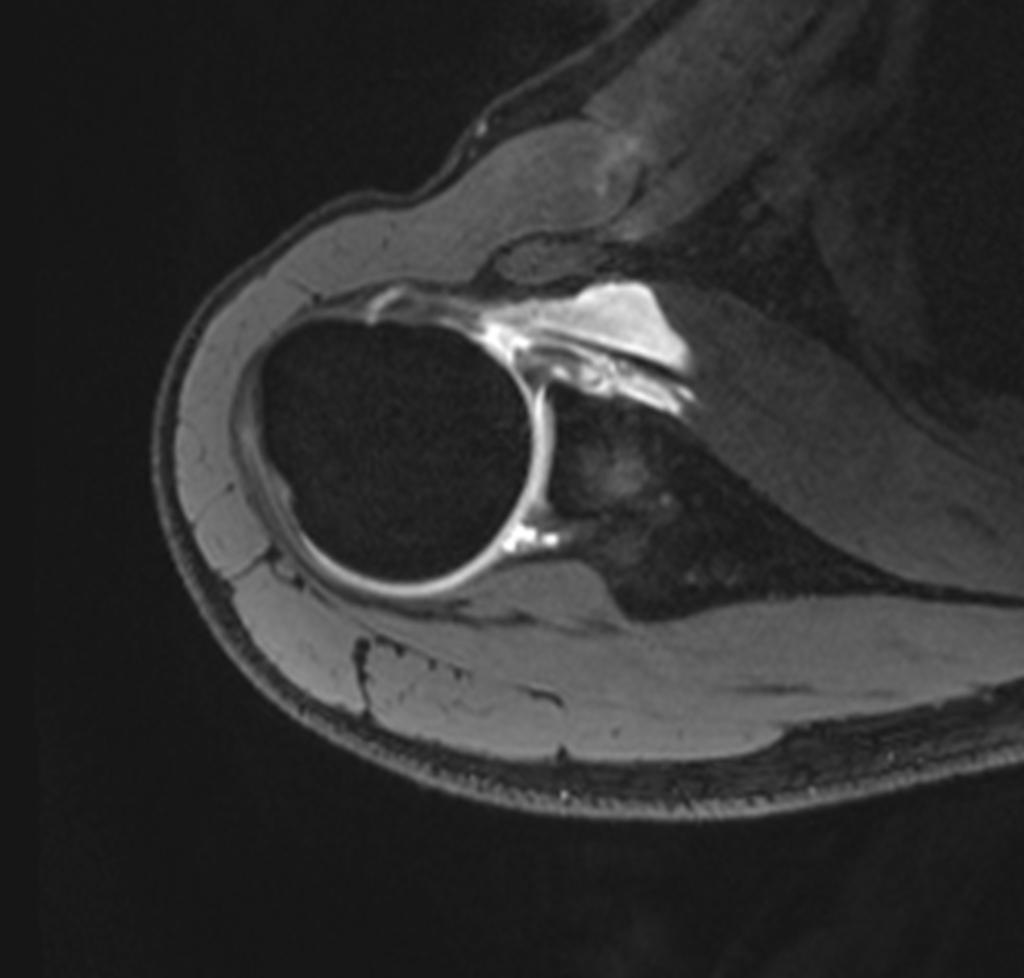

Labrumriss Schulter Ohne Op . Rehabilitation eines Labrumrisses der Schulter MedDe Die körperliche Untersuchung kann Hinweise auf einen Labrum-Riss liefern, der jedoch im Allgemeinen im MRT bestätigt wird. In der Zeit wird die Schulter passiv durch Physiotherapeuten bewegt

Source: amrusoftdqa.pages.dev Mri Shoulder Labrum Tear , Januar 2018 , Anna Gabriel Je nach Ausmass der Labrumläsion wird Ihr Arzt Ihnen zur physiotherapeutischen Behandlung oder einer Operation raten Bei einem Labrumriss kommt es zu Schulterschmerzen, einer eingeschränkten Beweglichkeit und einer eingeschränkten Stabilität der Schulter